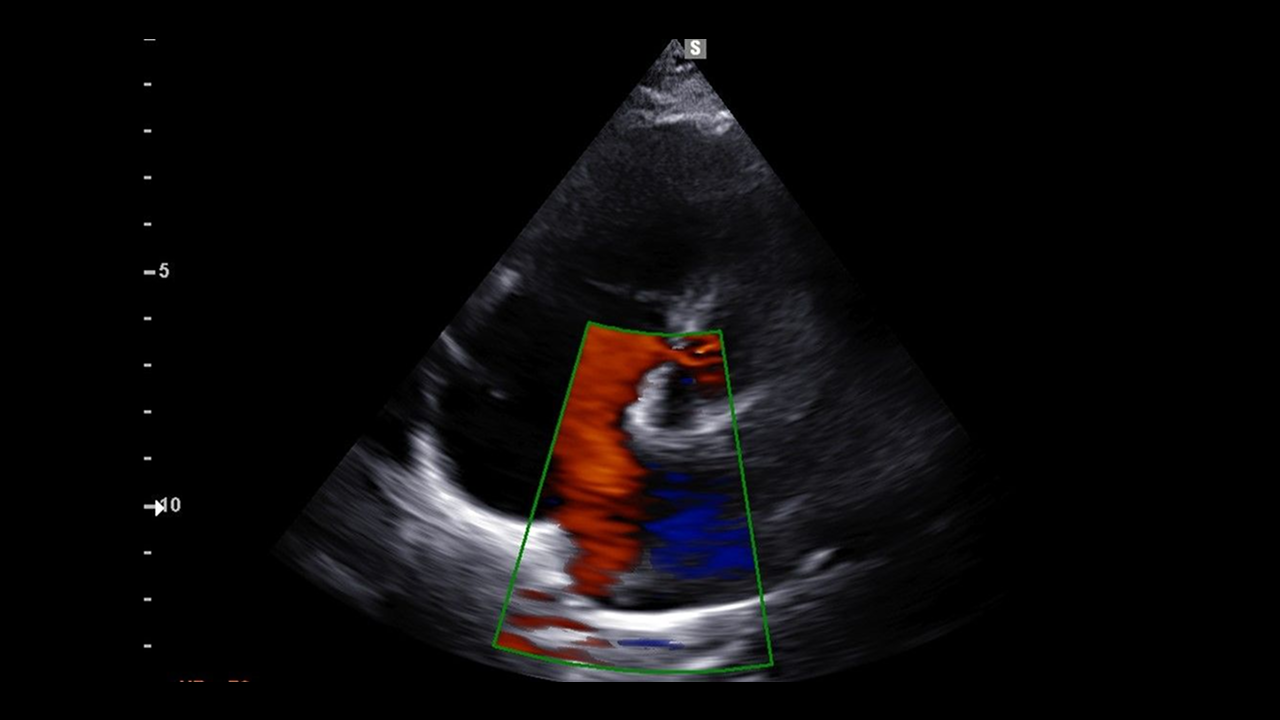

삼성탑내과 심초음파 검사안내

김포내과 삼성탑내과 심장초음파 검사안내심장초음파(Echocardiography)는 심장의 구조와 기능을 평가하기 위해 사용하는 비침습적 검사입니다. ✅ 검사방법: 초음파 푸르브(PROBE)에 젤리를 묻혀 검사를 진행합니다.✅소요시간: 경우에 따라 다를수 있지만 일반적으로 10분~30분 가량 소요 됩니다.✅통증 유무: 비 침슴적인 검사이므로 통증은 전혀 없습니다 **심장초음파의 주요 적응증(적응 대상)**✅ 1. 심잡음(Murmur)심잡음의 원인 감별 (판막 질환 여부 확인)✅ 2. 심부전 증상 평가호흡곤란, 하지 부종, 피로 등 → 심장의 수축 및 이완 기능 평가✅ 3. 심근경색 및 협심증심근의 운동 이상 여부, 좌심실 기능 평가✅ 4. 고혈압 환자의 심장 상태 평가좌심실 비대(hypertrophy), 이완기 기능 장애 여부 등 확인✅ 5. 판막 질환 의심 시승모판막협착증, 대동맥판막역류증 등 → 정확한 진단 및 중증도 평가✅ 6. 선천성 심질환심방 중격 결손(ASD), 심실 중격 결손(VSD) 등 진단✅ 7. 심낭 질환심낭삼출(pericardial effusion), 심장압전(cardiac tamponade) 여부 확인✅ 8. 심장종양 또는 혈전 의심 시심장 내 종물(mass), 혈전(thrombus) 감별✅ 9. 심인성 실신 평가구조적 심질환 여부 확인✅ 10. 심장 감염 질환감염성 심내막염(endocarditis) 의심 시 판막 위 식물(vegetation) 확인✅ 11. 심방세동(AF) 등 부정맥 평가기저 심질환(좌심방 확장, 판막 질환 등) 유무 확인✅ 12. 항응고 치료 전 심장 혈전 확인전기적 심율동전환(cardioversion) 전 좌심방 혈전 유무 평가 (특히 TEE 이용)필요 시에는 경흉부 심초음파(Transthoracic Echo, TTE) 외에도경식도 심초음파(Transesophageal Echo, TEE) 또는 운동부하 심초음파 등을 추가로 시행할 수 있습니다.✅ 삼성탑내과는 심초음파 경력 25년 으로 현재 대한 임상초음파학회 학술이사(심장)를 역임하고 있으며 대한 심초음파학회의 심초음파 인증의 자격을 보유하고 있습니다.